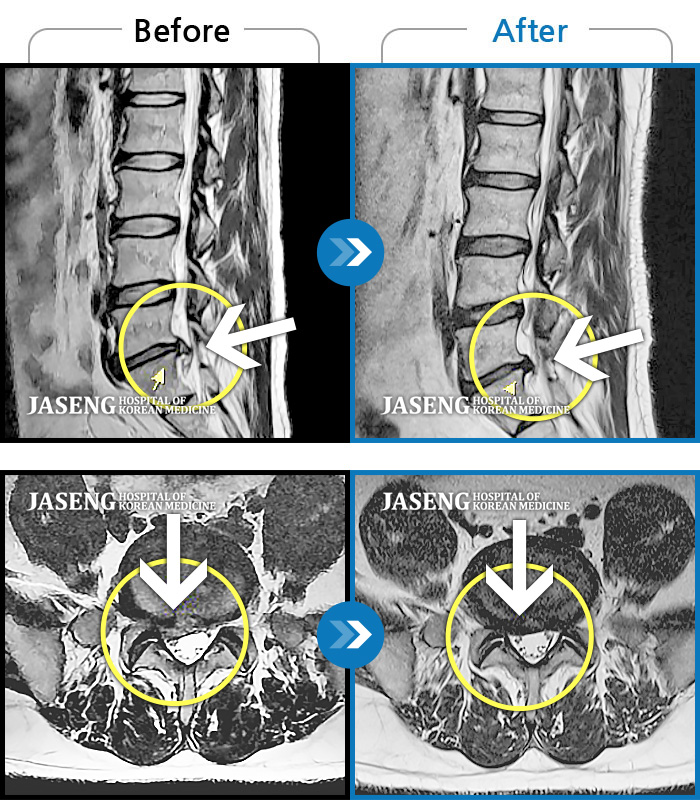

허리디스크

광주 · 김동은 원장

허리 통증과 양측 둔부부터 허벅지, 발목 부위 저리는 증상으로 내원하셨습니다.

촬영시기

2025.05.09 ~ 2025.12.18

2025.12.22